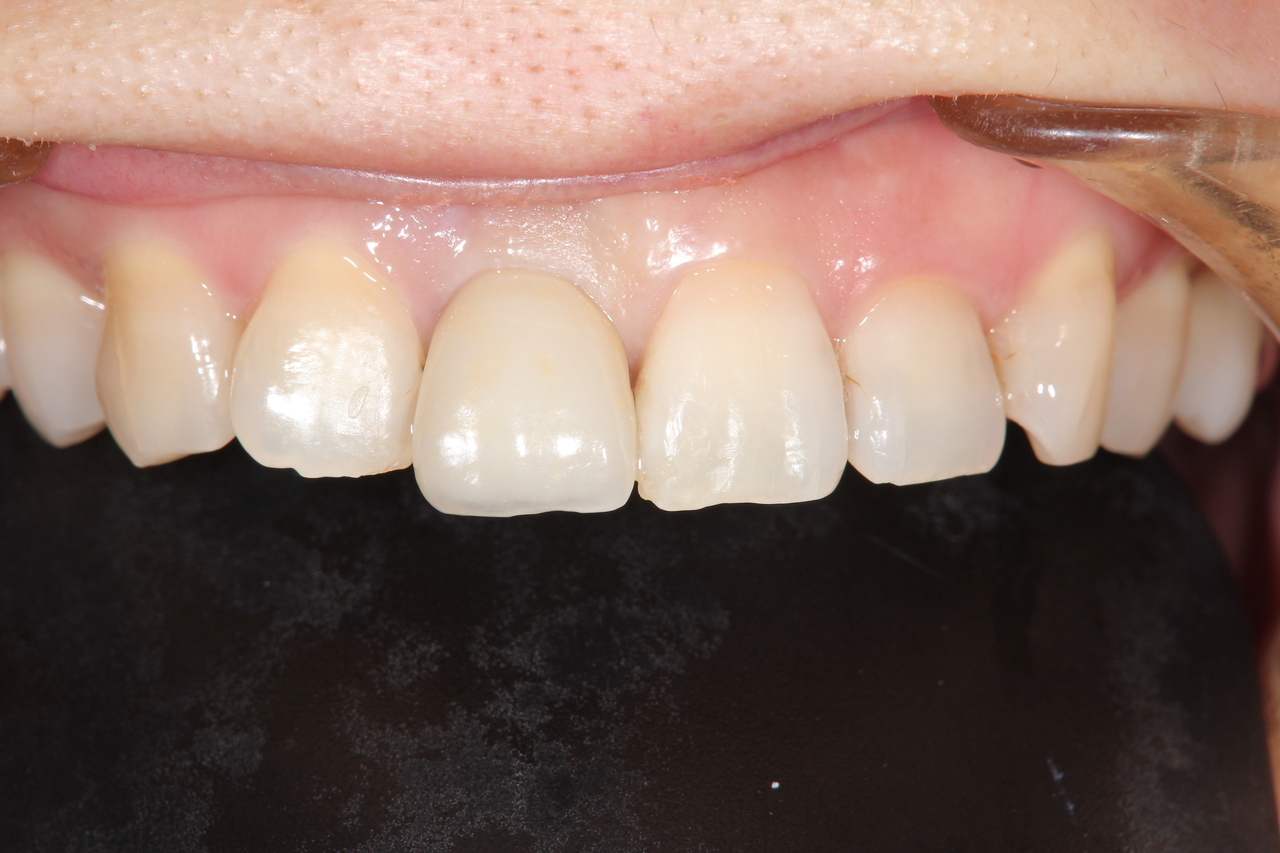

前歯インプラント(美しさを重視した場合は、ジルコニアでセメント固定がお勧めです。前歯の場合は、歯肉の形をシャープできれいな形にする為、仮歯が必要です。)

(下田市在住 女性)

治療の流れ

前歯破折

神経を取って差し歯にしていた歯根が破折したため、抜歯することになりました。

前歯インプラント土台

前歯部の審美領域は、白い土台など、より綺麗に見せるオプション費用が追加になります。

前歯インプラント

最終的な被せ物を装着すると、隣の天然歯と見分けがつかない綺麗な仕上がりになりました。